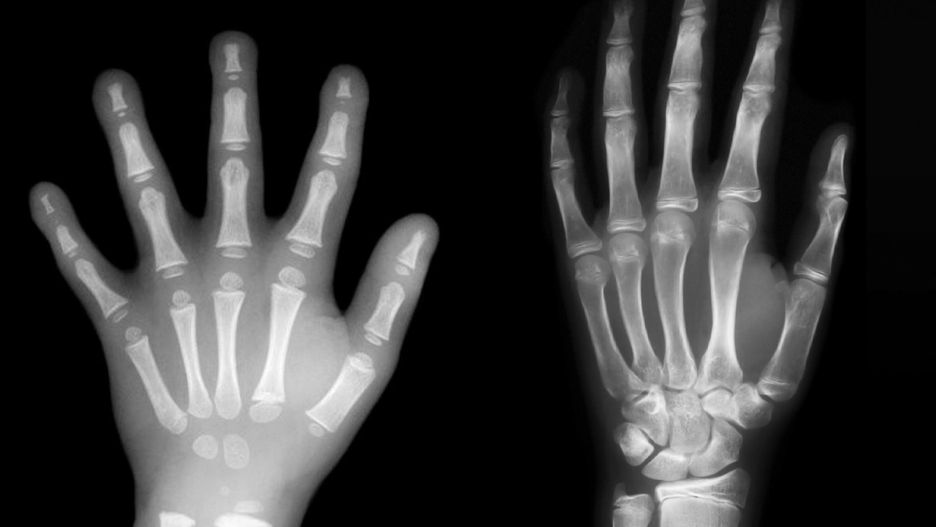

Dłoń przedszkolaka nie jest w pełni ukształtowana. Różnice w rozwoju widać gołym okiemDłoń przedszkolaka nie jest w pełni ukształtowana. Różnice w rozwoju widać gołym okiem

W pouczającym poście na Facebooku opublikowała także zdjęcie rentgenowskie dłoni dziecka w wieku przedszkolnym (po lewej) oraz siedmioletniego (po prawej). Różnice w układzie kostnym widać gołym okiem.

"Chcesz wiedzieć, dlaczego dziecko w wieku przedszkolnym nie potrafi jeszcze pisać? Dlatego! Jego ręce wciąż się rozwijają i nie są w pełni ukształtowane – pisze Millie. - Więc co powinniśmy zrobić, aby wesprzeć rozwój? Dać mu się bawić!" – dodaje.